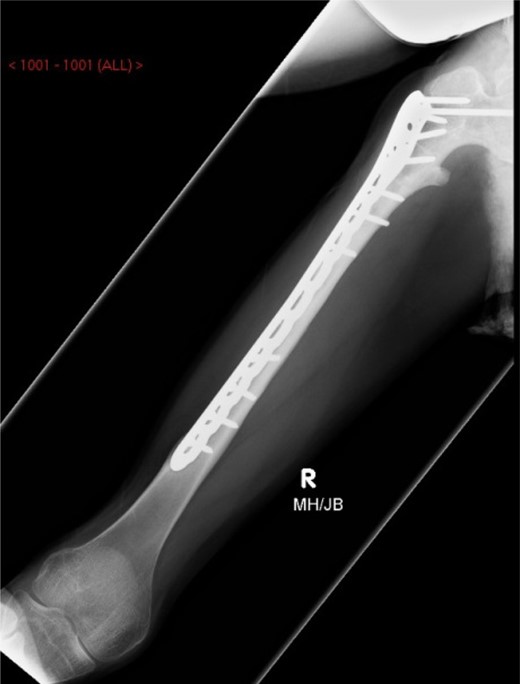

Under general anaesthesia, open reduction and internal fixation using a 10 hole philos plate was performed with the patient in a supine position on the traction table utilizing a lateral approach. Using C-arm image intensification, the height of the plate was judged, then applied to the bone and secured both proximally and distally to the fracture with proximal locking screws inserted where possible (Fig. 2a–c). Securing the cephalic segment of the philos plate to the proximal femur proved challenging due to the femoral neck defect left by the removal of the blade plate. Final reduction was judged to be near anatomical with the wound thoroughly irrigated with saline before closure. Post-operative treatment included IV antibiotics with mobility instructions unnecessary due to the patient's non-ambulatory status. The patient was discharged after 5 days with a follow-up period over 11 months. There were no post-operative complications during this time and radiographs showed an anatomically healed fracture (Fig. 3).

Image intensifier intra-operative AP highlighting 10 hole PHILOS applied with near anatomical reduction (a–c).

AP-XR demonstrating radiographic union at 11 months with 10 hole PHILOS insitu.